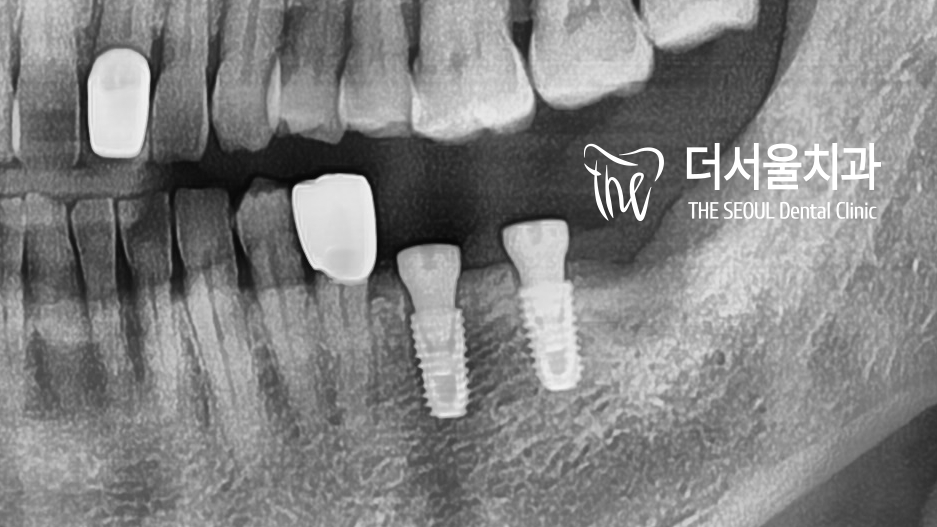

『3차원 컴퓨터 분석을 통한 식립』

염증 및 잔존조직들을 깨끗하게 제거하고

컴퓨터 분석에 들어갔습니다.

총 2곳에 픽스쳐를 심은 다음

인접한 크라운을 교체하기로 했는데요.

식립 방향과 위치, 사용될 픽스쳐의 종류를

꼼꼼하게 분석하여 결정한 뒤,

약간의 골이식을 동반하여 픽스쳐를 심었습니다.

*염증으로 인해 치조골 소실이 나타나

골이식재를 동반하여 식립하기로 함.

튼튼하게 결합이 잘 된 것을 볼 수 있죠?